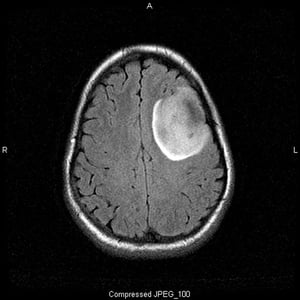

Questa scansione RM T2-FLAIR (fluid-attenuating inversion recovery) mostra un segnale bianco, che può indicare una massa o edema. Il segnale frontale sinistro è altamente demarcato, suggerendo una massa. L'uso del contrasto non lo migliora. È un oligodendroglioma di basso grado (grado II).

Image courtesy of William R. Shapiro, MD.